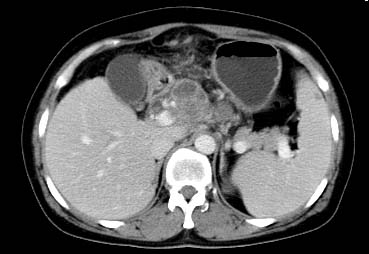

以下是引用西北一只狼在2008-6-30 20:58:00的发言:[br]肝左叶胆管细胞ca并肝门淋巴结转移、胰腺、胃小弯浸润

以下是引用ydx_74在2008-6-30 21:54:00的发言:[br]左叶胆管细胞ca并肝门淋巴结转移、胰腺、胃小弯浸润